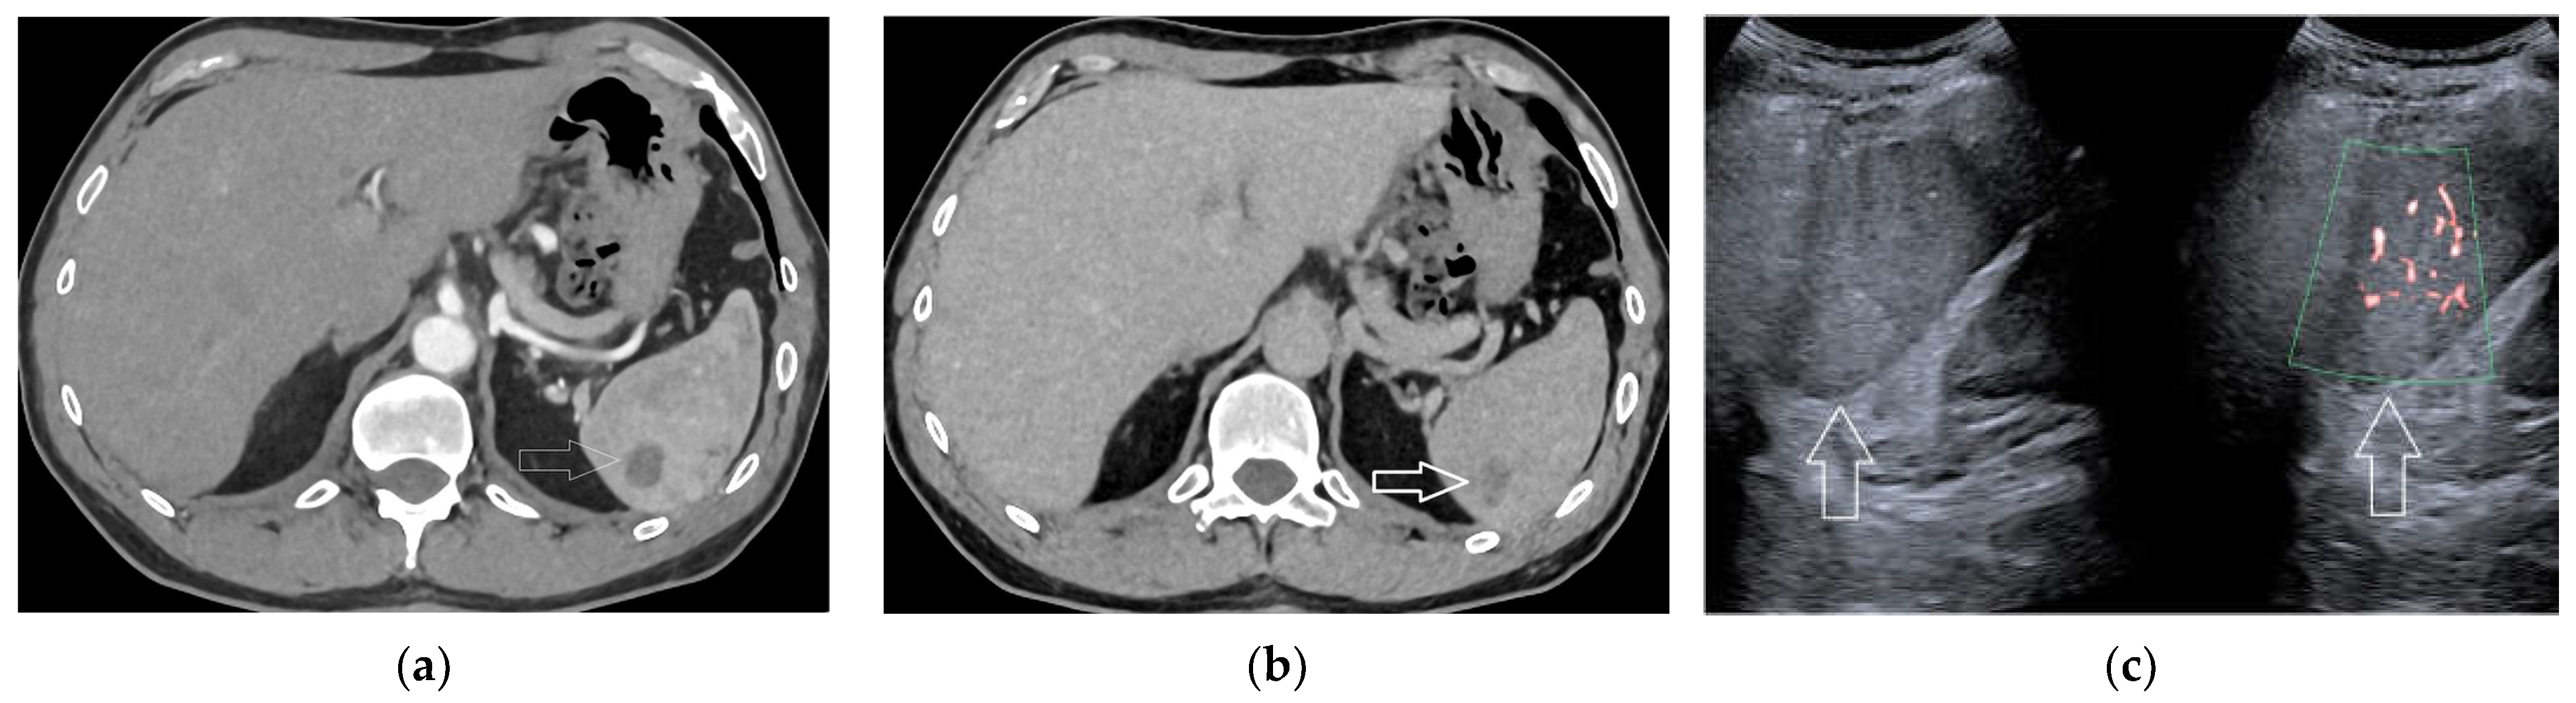

2.6. Infarcts

2.7. Solid Lesions